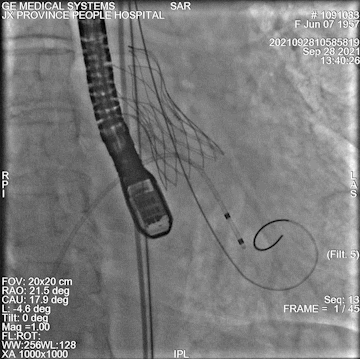

瓣膜定位

释放后

术中情况:术中超声及造影评估,左冠灌注未受影响,瓣膜释放后无明显下滑,洪浪院长术中使用VitaFlow Liberty™进行操作,并精准释放,超声及时辅助评估,VitaFlow二代可回收功能给术者增加信心,可以更放心、大胆的挑战高风险病例。